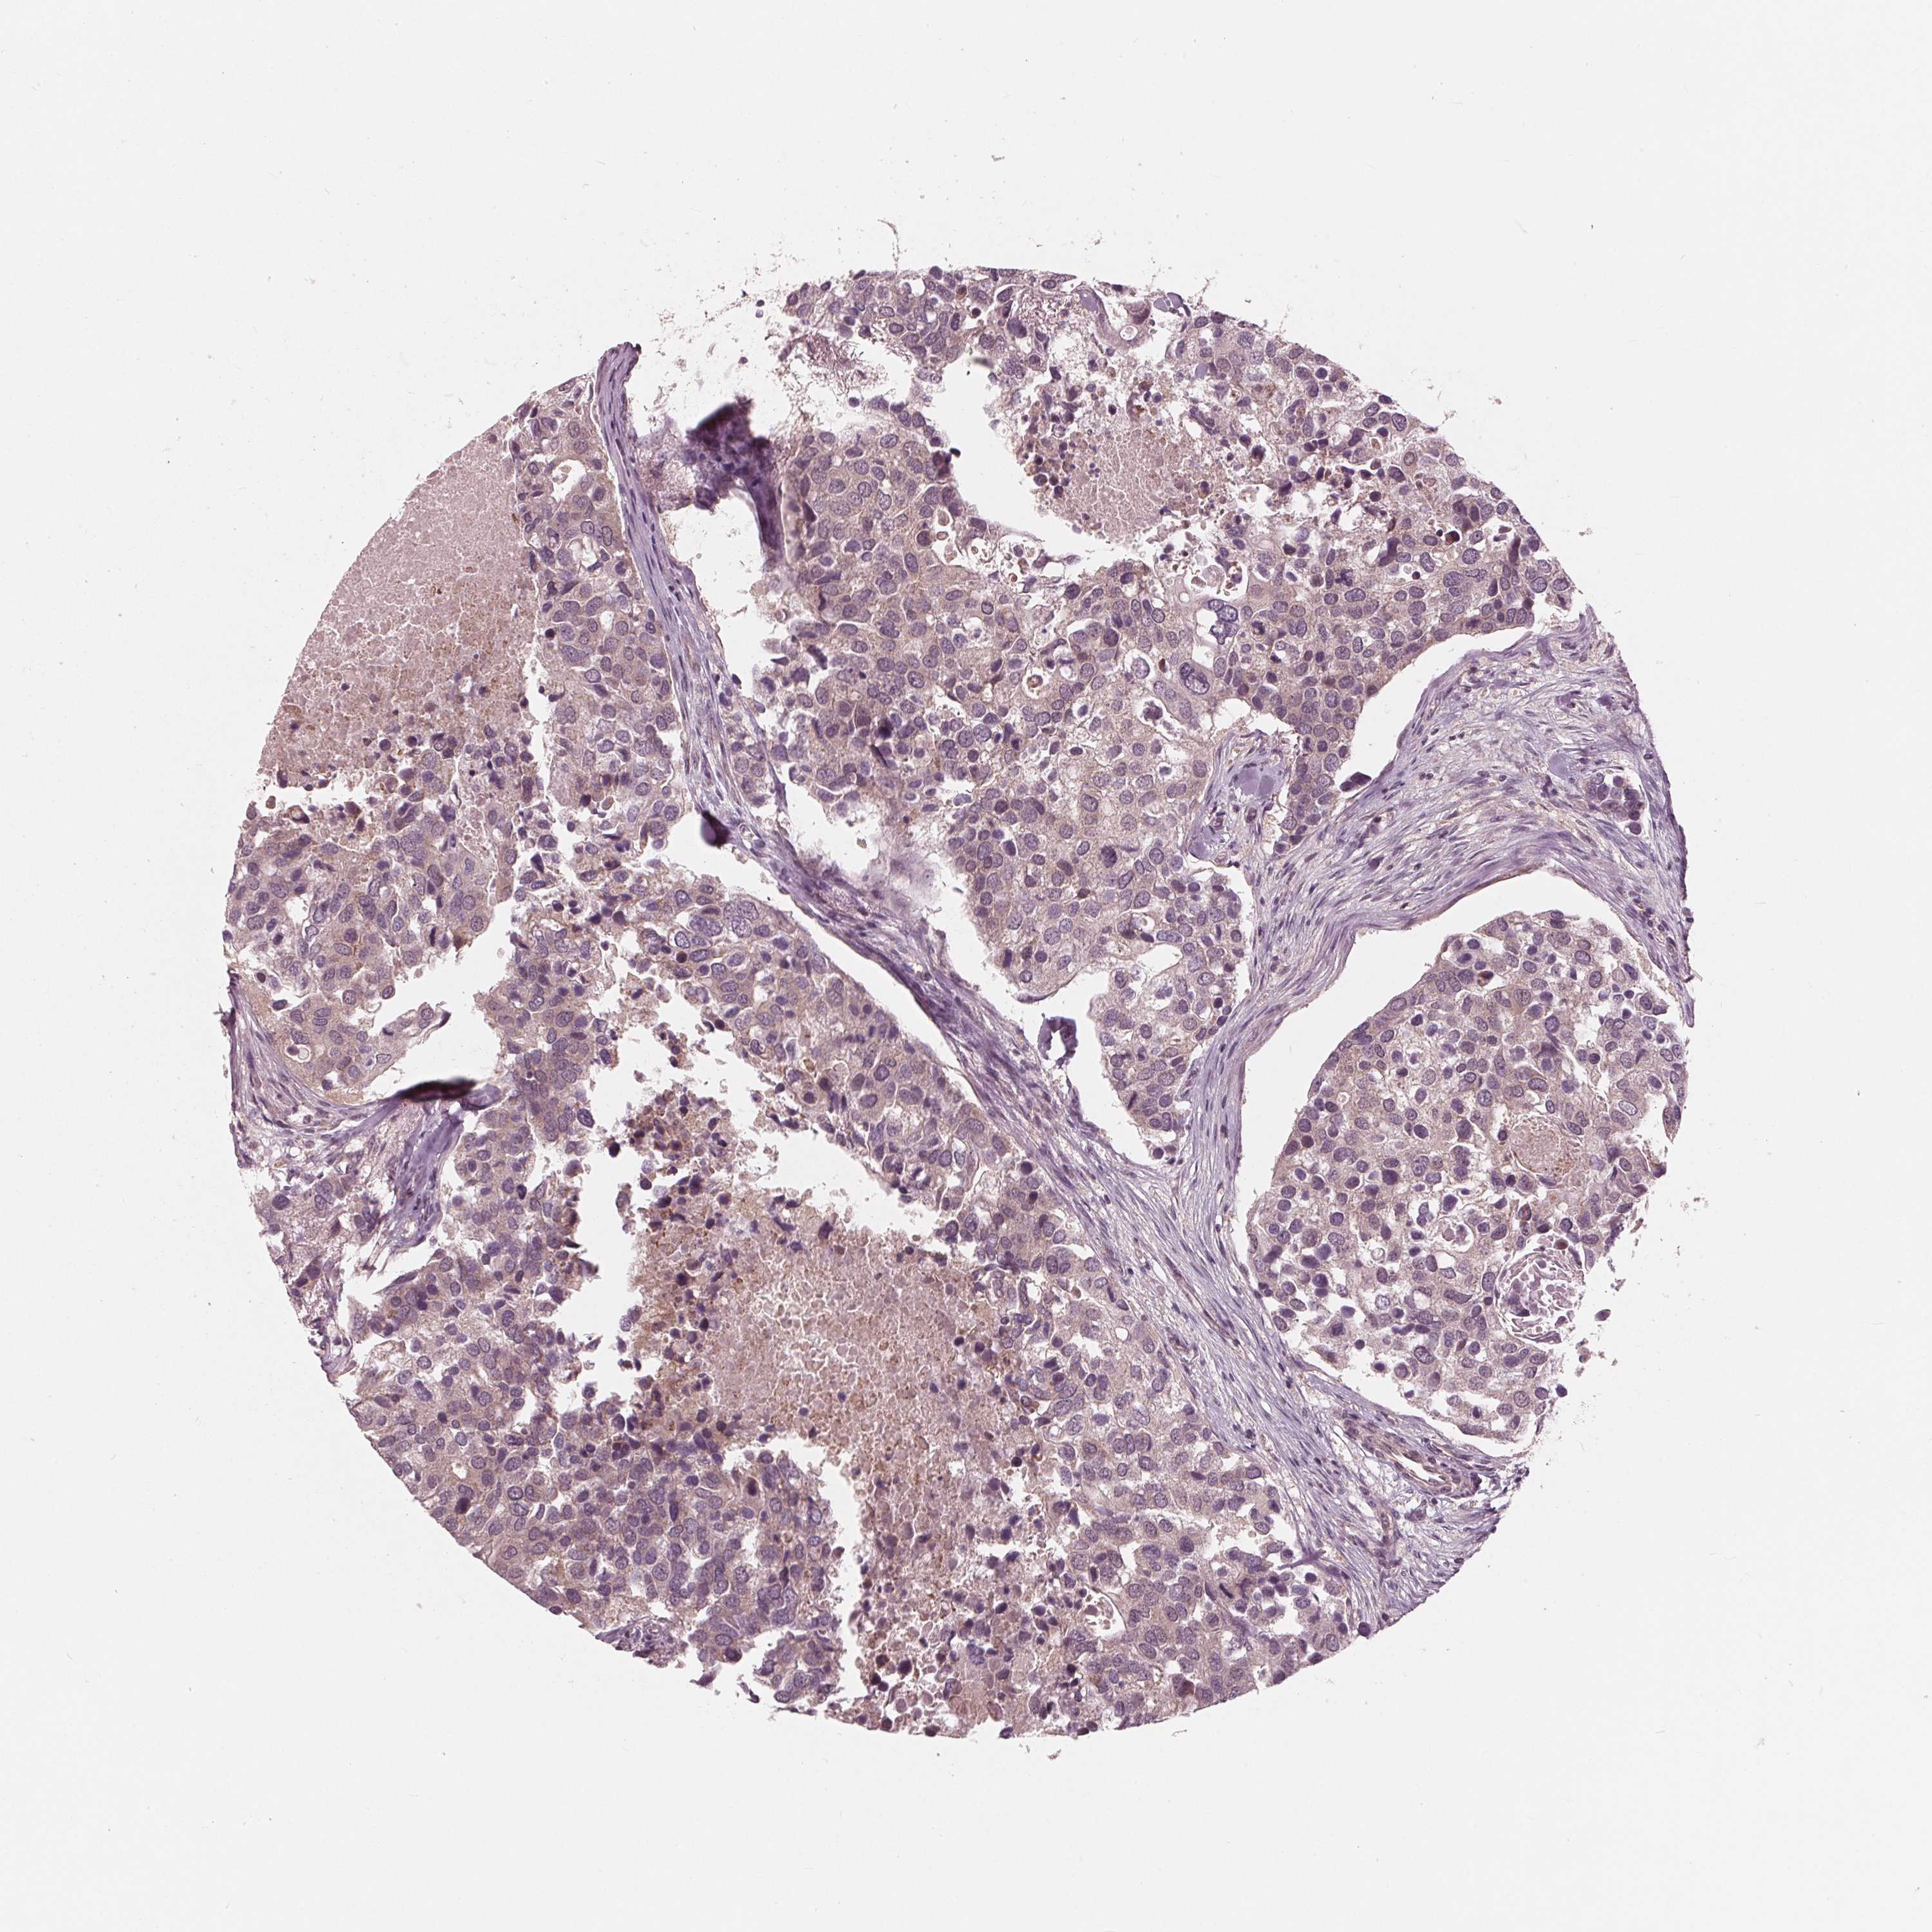

CANCER BREAST CANCER Show tissue menu

Breast cancer

Human cancer